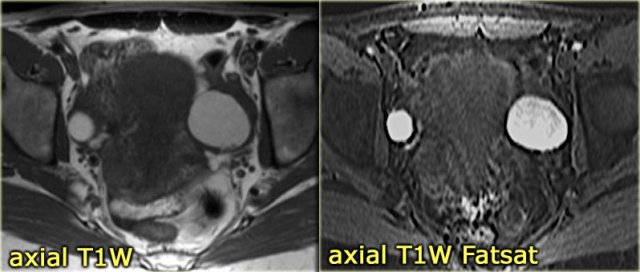

The next case is a unilocular, mildly hypoechoic ovarian lesion with through transmission.

There is no internal or wall vascularity on Doppler.

On ultrasound this can again either be a hemorrhagic cyst or an endometrioma.

Continue with the MR images

Endometrioma Endometrioma

6 months later a follow-up MRI was performed.

The lesions are bright on T1-weighted images.

The bright signal persists on fat saturation indicating the presence of blood.

There is T2 shading consistent with a hemorrhagic lesion.

There is no enhancement.

The fluid-fluid level in the right ovarian lesion also confirms its cystic nature.

The fact that the lesions persist after 6 months makes bilateral endometrioma much more likely than hemorrhagic cysts.